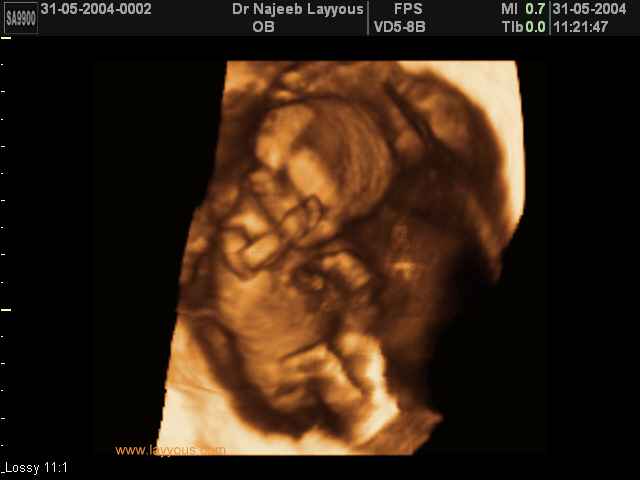

3D First Trimester Ultrasound Scan Photos